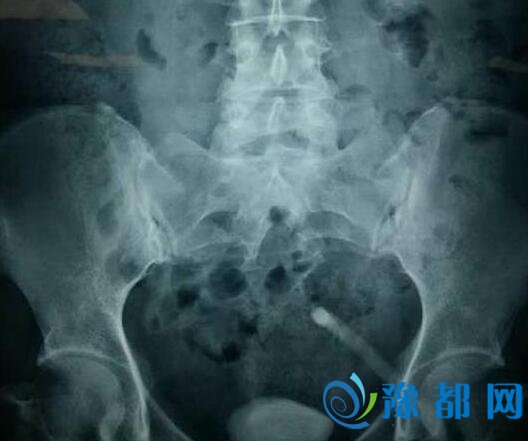

米教授经过会诊,结合康女士的症状,建议做膀胱镜、X光检查。经过细致检查后,米教授发现康女士膀胱内有一个鸡蛋大小的结石。米教授说,在他几十年的职业生涯中,对如此巨大的膀胱结石也比较少见。如何顺利取出结石,且患者能尽快康复成为医生们的难题。

图:微创经尿道膀胱结石钬激光碎石手术中

专家组经讨论后,决定对该患者进行微创经尿道膀胱结石钬激光碎石术。手术虽然棘手,但是专家组凭借多年的手术经验,和精湛的技法,使用钬激光逐步蚕食,将鸡蛋大小结石碎成粉末排出体外。手术大约持续两个小时。术后第二天,康女士便能自行下床活动。